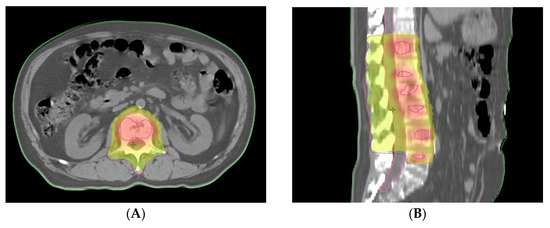

2. Detailed Case Description